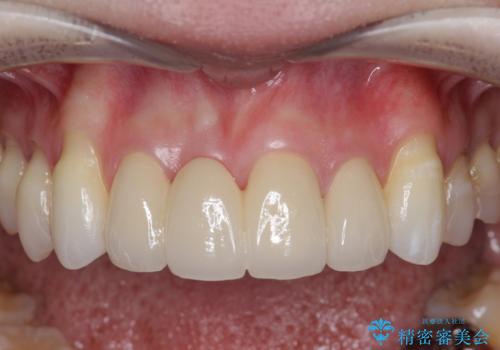

上顎4前歯は、根管治療の既往があり、虫歯も見られたことからブリッジによる治療で審美性の回復を行うとともに臨在歯の虫歯もセラミック治療を行っていきます。

- 44万円(仮歯・ジルコニアクラウン×4)費用は治療当時の料金となります

欠損部の歯ぐきの量が足りない場合は、移植を行い歯肉を増大させることもありますが、今回は仮歯で様子を見た結清掃性・審美性に問題が出なかったので行いませんでした。